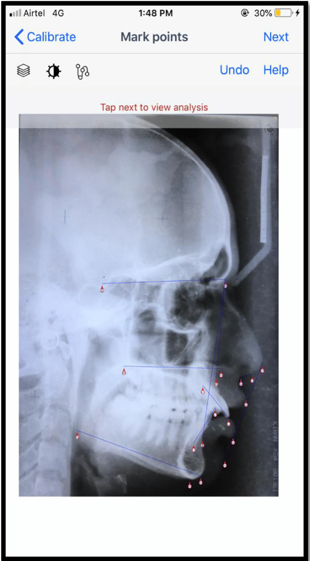

Figure 1 is a screenshot taken from the smartphone application cephNinja showing the various parameters used in the study. Figure 2 are the obtained measurements of the various parameters from the smartphone cephNinja application.

Figure 1 Screenshot taken from the smartphone application cephNinja showing the various parameters.

1)Point S (sella), 2) Point N (nasion), 3) Point A (A), 4)Point B (B), 5) Gonion (Go), 6) Gnathion (Gn), 7) Upper Incisor Edge (U1i), 8) Upper Incisor Root Apex (U1r), 9) Lower Incisor Incisal Edge (L1i), 10) Lower Incisor Root Apex (L1r), 11) Posterior Nasal Spine (PNS), 13) Anterior Nasal Spine (ANS), 14) Columella of the Nose (i.e. the mid-point between the subnasal point and the nose tip), 15)Upper Lip (UL), 16) Lower Lip (LL) and 17) Soft Tissue Pogonion (Pog’), 18) menton (me), 19) subnasale (Sn), 20) nasal tip (NT).